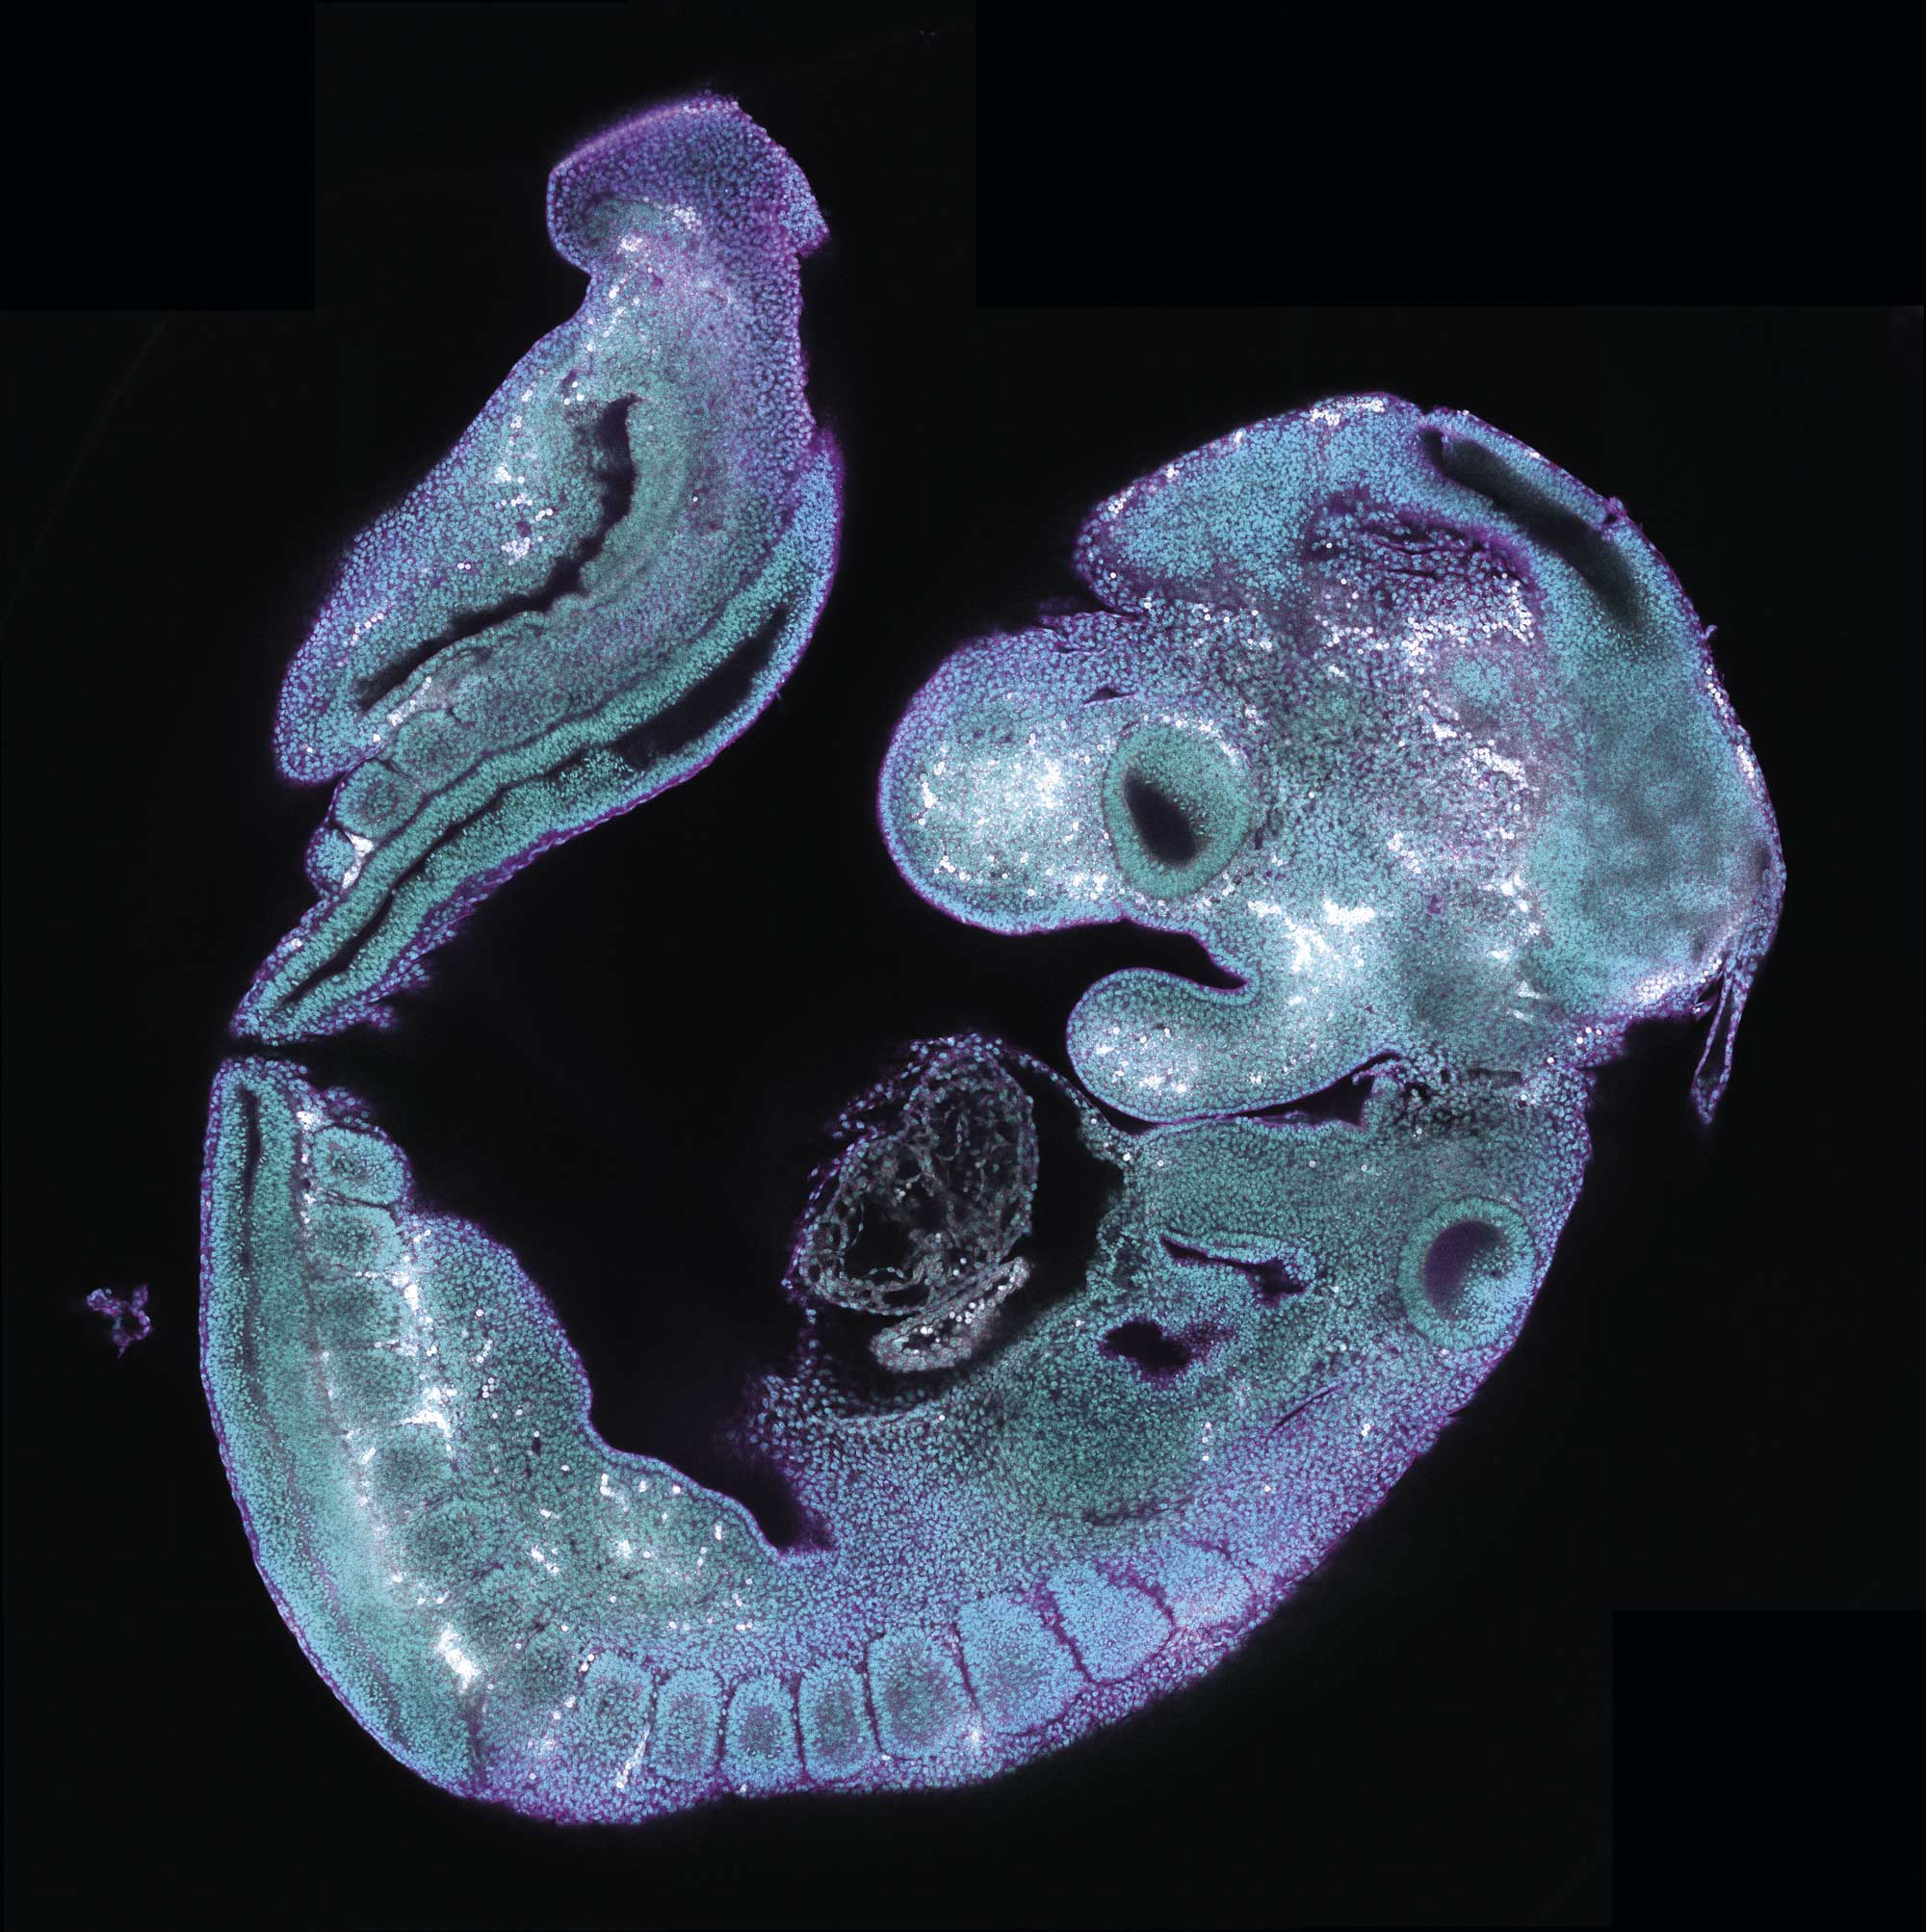

The Cardiovascular Regeneration Program (CVRP) aims to understand the fundamental principles of heart and vasculature development and regeneration, using this knowledge to develop new therapeutic strategies for cardiovascular diseases. A key focus of the program is the metabolic regulation of cardiac regenerative ability. In 2024, the CVRP made significant progress, uncovering new targets and therapeutic approaches.

Cox7a1-Deficient Zebrafish: Nadia Mercader and Jose Antonio Enríquez’s groups joined forces to study Cox7a1- deficient zebrafish, demonstrating the critical role of Cox7a1 in striated muscle homeostasis. Interestingly, the Cox7a1- deficient fish exhibited improved cardiac regeneration capacity, highlighting the importance of the modulation of super-complex their formation for the control of cardiomyocyte proliferation, as well as identifying a potential target for pro-regenerative strategies (Developmental Cell, 2024).

Single-Cell Resolution Tools: Rui Benedito’s group developed advanced tools in mouse models, enabling precise genetic dissection of molecular pathways at singe-cell resolution in vivo (Nucleic Acids Res, 2024; Nature Methods, 2024).

Bicuspid Aortic Valve Genetics: Jose luis de la Pompa’s group uncovered new genetic determinants of bicuspid aortic valve and began characterizing genes involved in ventricular wall maturation and cardiomyopathy (Disease Models and Mechanisms, 2024).